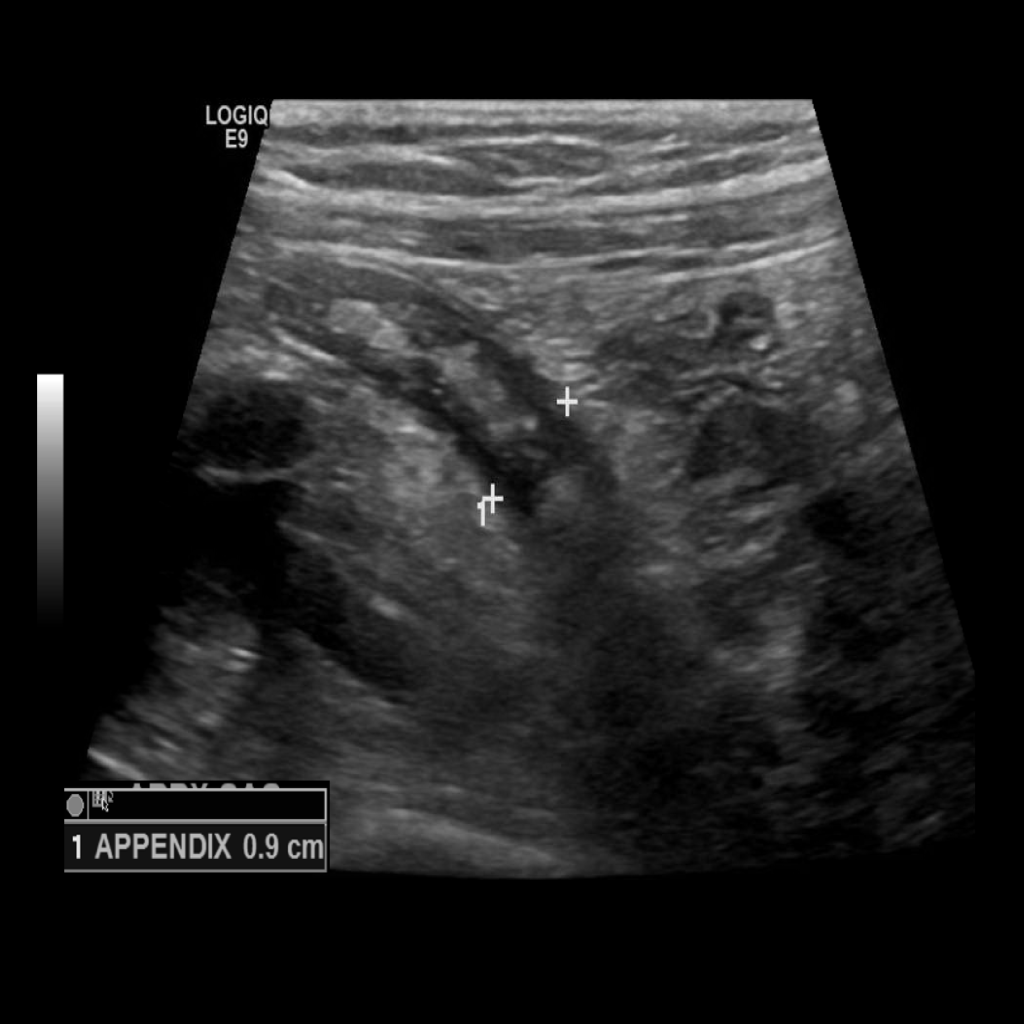

Appendicitis 12

0.9 cm positive appendicitis, with peripheral free fluid, and fat stranding.